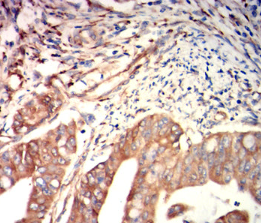

FGL1 Mouse Monoclonal antibody[4F9C1]

Species Reactivity:    Human

IHC    1/200-1/1000